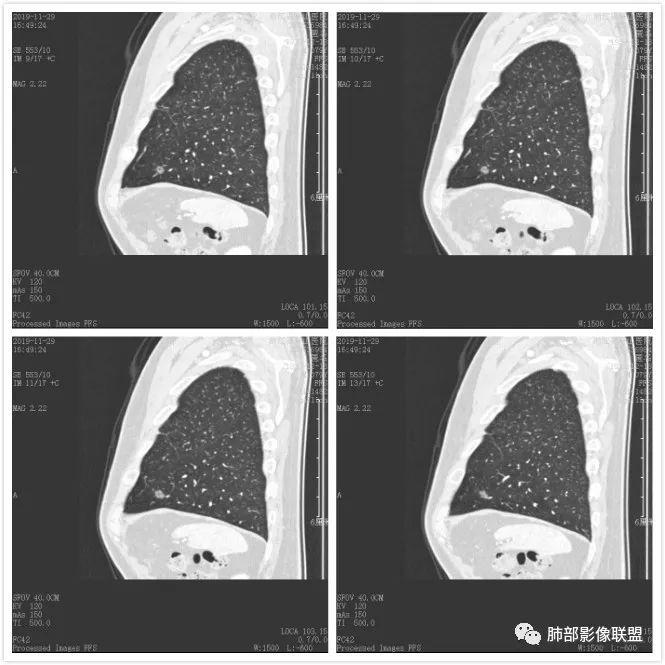

病例2

混合磨玻璃,内血管粗,空泡。MIA-LPA? 医学百科网 | YxBaike.Com

右肺上叶两个磨玻璃结节,内可见小空泡,边缘清晰,血管进入增粗,考虑MIA

两个病灶内都有小泡征 医学百科网 | YxBaike.Com

支持mia,空泡罪加一等

混合磨玻璃结节,可见空泡征,MIA

大的考虑MIA至LPA

大的,有空泡,MIA,小的,AIS 医学百科网 | YxBaike.Com

病理诊断 MIA 浸润性微腺癌